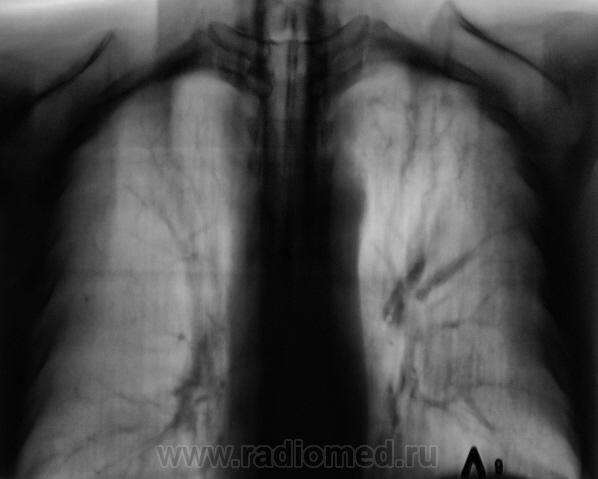

При расшифровке флюорограмм пациент "взят на контроль". Жалоб пациент не предъявляет. Подняли "архив", флюорограмма за 2009 г. - "норма".

Произвели стандартное дообследование.